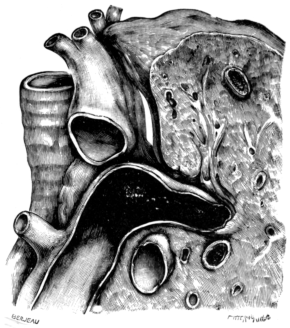

| 268. | Anatomy of the Larynx and Trachea and the Position of Incisions for the Operations in this Region | 525 |

| 262. | Total Laryngectomy | 498 |

| 263. | Total Laryngectomy. Gluck’s Method | 501 |